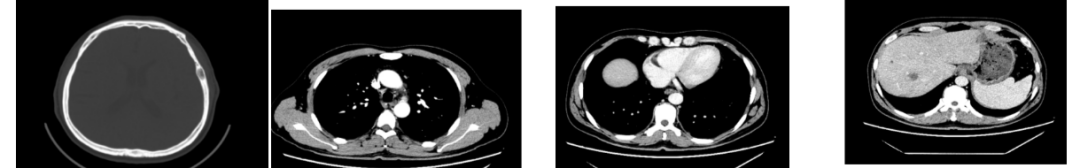

2018-11-14 CT(8周期化疗后):PD?

△基线水平

△治疗后

增强CT示:肝硬化

肝异常强化灶

胃癌并肝转移化疗后,肝内转移灶大致同期;

慢性肝病,脾大、门脉高压(食管下段-胃底静脉曲张);

右肺上叶前段实性微小结节,炎性结节?建议定期复查;

纵隔淋巴结转移瘤,复查大致同前。